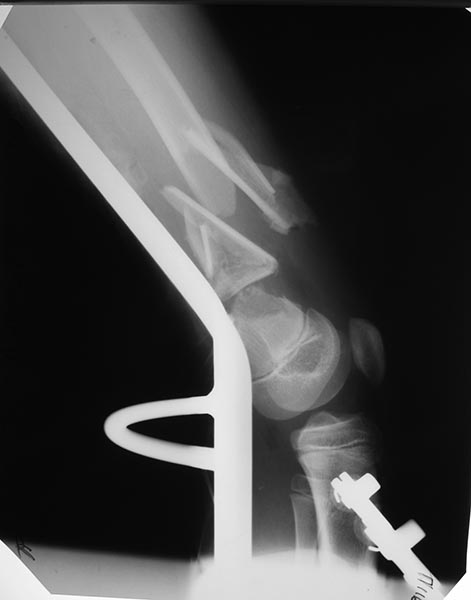

Переломы оскольчатые обеих бёдер в н/3, открытые. Раны ушиты в отличном состоянии.

На одном бедре межмыщелковый перелом и там мыщелки немного разъехались. Голень там тоже сломана в н/3 обе кости. Снимок голени в боковой проекции сделан не был.

Сложный случай. Я бы попробовал бедро с межмыщелковым переломом синтезировать закрыто мыщелки канюлированым шурупом(надеюсь он у Вас есть)и 4-5 спицами антеградно с н/3 диафиза бедра(в идеале под ЕОП контролем).Второе бедро- открыться, стержень Богданова,спицу в дистальный фрагмент через отверстие в стержне,серкляж. Коксит обязательно.Голень тоже нужно репонировать(вальгус слишком большой)и синтезировать спицами антеградно.

Глубокоуважаемый Игорь. Есть ли в вашем отделении ЭОП? Переломы бёдер не простые. Я бы не стал рассчитывать на скелетное вытяжение. Не очень понятно где какое бедро. Левые снимки – по моему мнению бедро надо оперировать с артротомией: необходимо убрать осколки по передней поверхности перелома – они гарантировано будут мешать движениям. Малоинвазивное удаление может быть неудачным. Синтез мыщелков имеющимися у Вас спицами под контролем глаза и пальца. Кстати, в суставе могут быть обнаружены различные неожиданности. Общую фиксацию можно осуществить в АНФ Илизарова с встречной компрессией мыщелков. Правые снимки. Тоже высокоэнергетический перелом и критическое смещение отломков. Так оставлять, ИМХО, не стоит. Велика вероятность массивной интерпозиции между отломками. Отломки ротированы и это может вызвать нарушение сращения,ремоделирования кости. В качестве варианта: наложение АНФ Илизарова, разрез, «ручная» репозиция отломков «по месту». Дистальные перекрещивающиеся спицы я бы провёл через мыщелки бедра. АНФ будут оптимальны в спице-стержневом исполнении. С уважением!